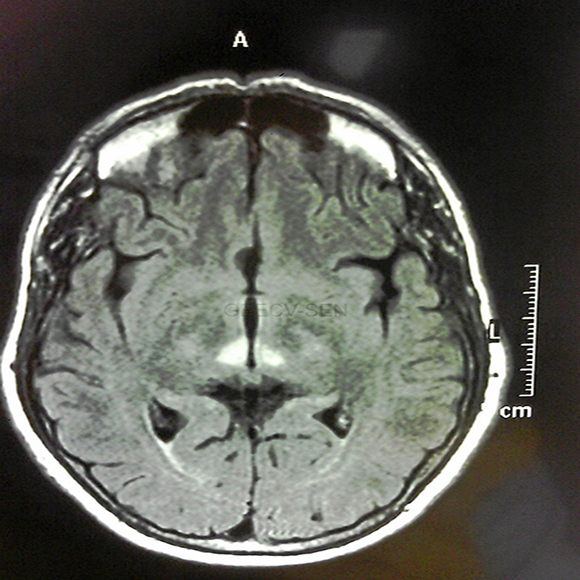

Reducir el glutamato en sangre disminuye el tamaño de ictus

Un estudio ha demostrado que en ratones tratados con riboflavina, la reducción de glutamato en sangre se asoció con una disminución del tamaño del ictus.